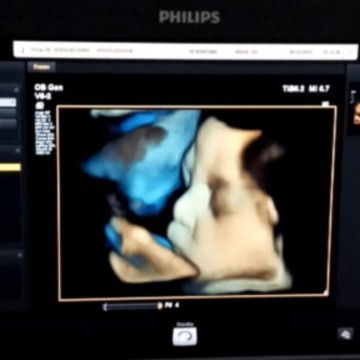

It's a boy😍 33week

insha allah baby boy